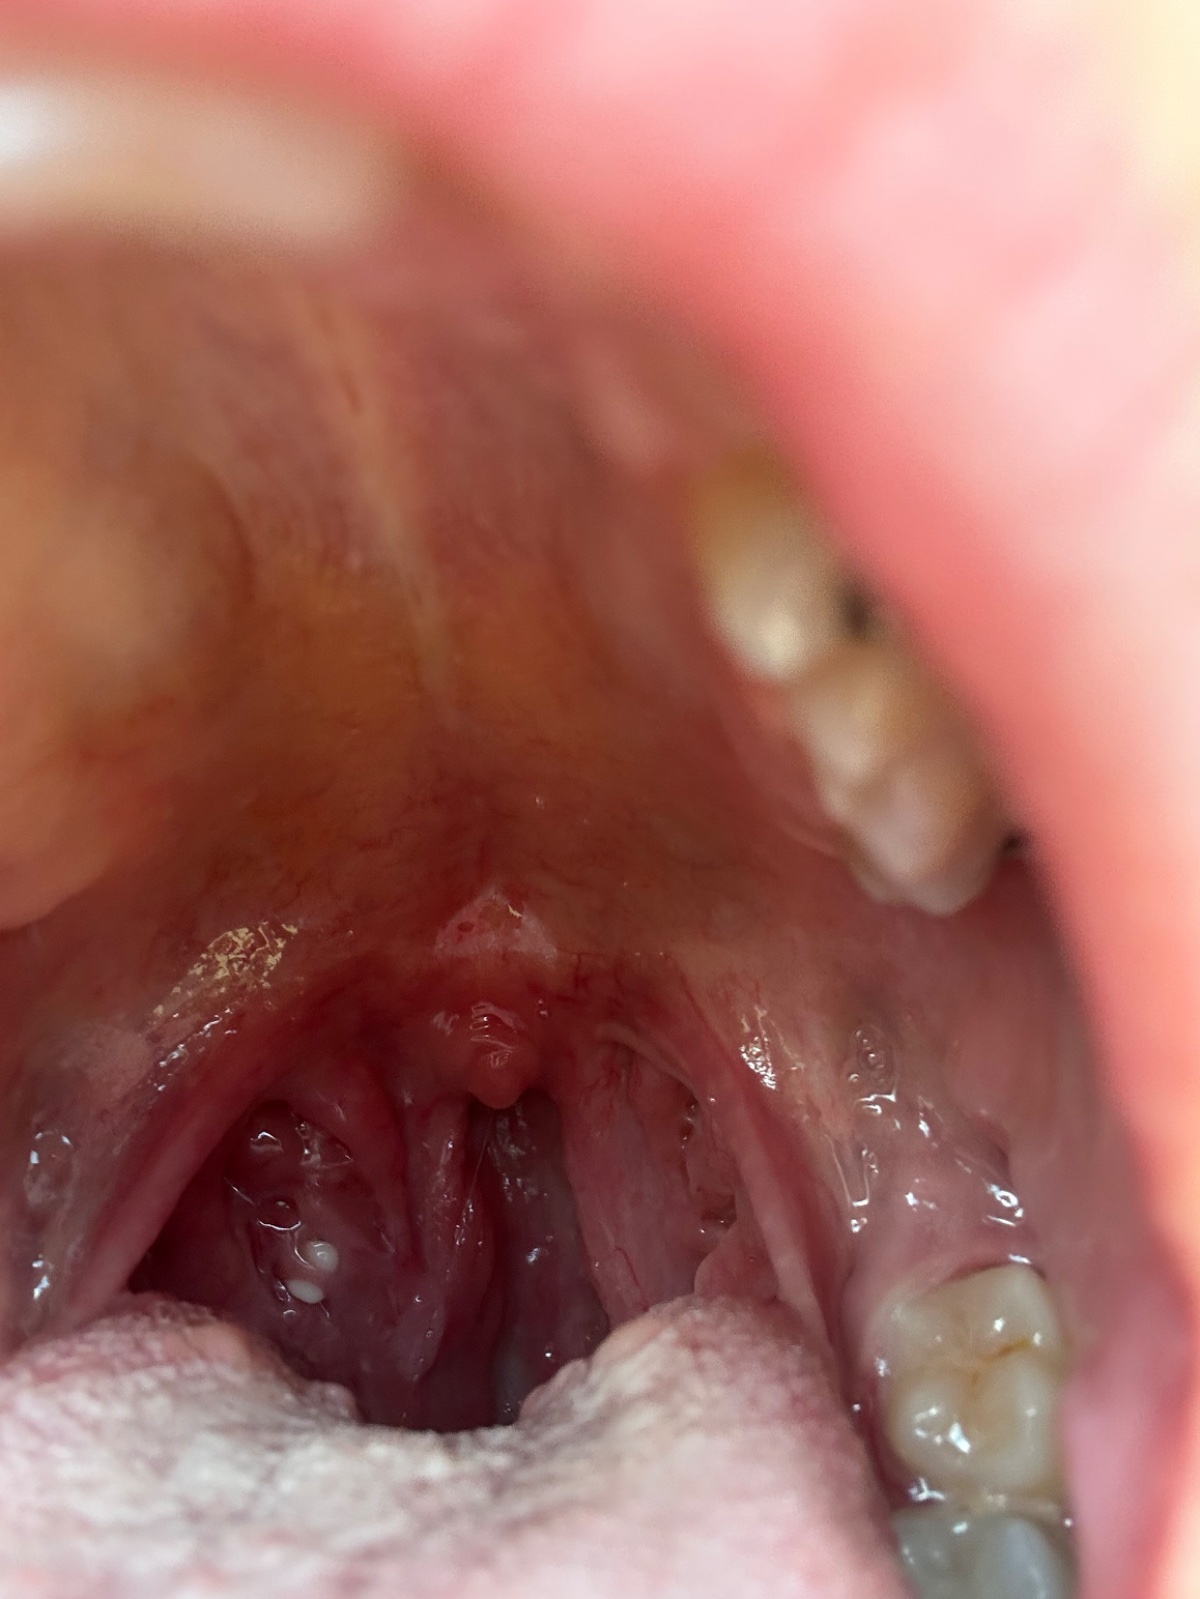

Už od februára riešim červené hrdlo a takéto uzliny. Netuším či mám obe zväčšené alebo len jednu no na tej strane kde mám tie biele čapy ma boli ucho. Vlastne neboli len v ňom stále cítim pulzovanie ako keby som počula srdce. Niekedy až tak že sa neviem na nič iné sústrediť. Stipe ma aj jazyk.

Riešim to v podstate 5 mesiacov a žiadne zlepšenie len zhoršenie stavu. hrdlo ma neboli len niekedy ako keby škriabe. Ale vždy keď prehltnem pukne mi v uchu.

Vyzerá to ako mandľový kameň. Aj to môže robiť tieto problémy